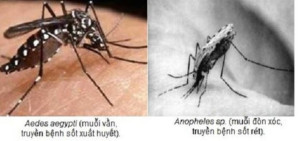

Hiện nay, số ca mắc sốt rét và sốt xuất huyết đều tăng. Người dân cần phân biệt được triệu chứng của hai loại bệnh cũng như cách phòng tránh để bản...